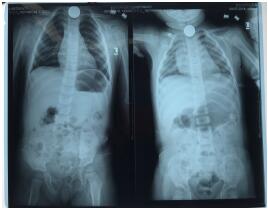

2名小孩誤吞的硬幣都卡在食管入口處,為食管第一狹窄部位,硬幣活動(dòng)度差,鏡身難以控制,取異物耗時(shí)長(zhǎng),患兒難以配合內(nèi)鏡操作,故需于麻醉狀態(tài)下進(jìn)行。由于嬰兒口腔及食道較成人狹小,最小的咬口也無(wú)法塞進(jìn)患者的口腔,醫(yī)務(wù)人員使用5ml注射撐開(kāi)兒童的口腔,選擇纖細(xì)的支氣管鏡,在多次嘗試進(jìn)鏡后,將5角硬幣順利取出。